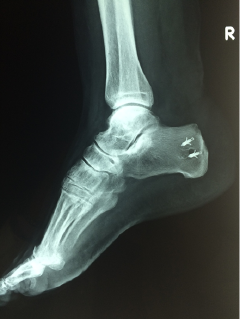

Νόσος Haglund

Πρόκειται για πάθηση που αναπτύσσεται στην κατάφυση του αχιλλείου τένοντα στο πίσω μέρος της πτέρνας. Η περιοχή είναι συνήθως ιδιαίτερα επώδυνη και διογκωμένη λόγω υπερόστωσης (οστικής υπερτροφίας) στην κατάφυση του αχιλλείου. Τα ενοχλήματα μπορεί να συνδυάζονται με πόνο στην περιοχή του πέλματος. Η πάθηση συχνά συνοδεύεται από τενοντίτιδα του αχιλλείου, που καθιστά την θεραπευτική προσέγγιση δυσκολότερη.

Οι ανθιστάμενες στη συντηρητική θεραπεία περιπτώσεις έχουν ένδειξη για χειρουργική αντιμετώπιση. Η κατάφυση του αχιλλείου αποκολλάται, η υπερόστωση αφαιρείται, ο αχίλλειος επανακαθηλώνεται συνήθως με διοστικές άγκυρες, και αν υπάρχει χρονία τενοντίτιδα του αχιλλείου μπορεί να χρησιμοποιηθεί ένας τένων από του καμπτήρες του άκρου ποδός (συνήθως ο μακρός καμπτήρας του μεγάλου δακτύλου) για ενίσχυση.

Μετεγχειρητική